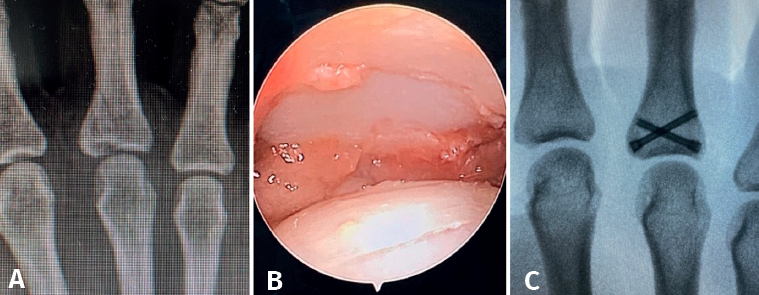

Arthroscopy of the MCP joint allows extensive visualization of the metacarpal head and the base of the proximal phalanx (Figure 1).

In terms of treatment, different authors advocate debridement of the insertional area of the ligament, reduction and correct positioning of the bone fragment, and its percutaneous fixation with Kirschner wires(1). Other authors advocate arthroscopy to locate and prepare the ligament and, by means of a minimal incision, re-anchor it(9).

Arthroscopically assisted reduction and percutaneous fixation of the avulsed fragment has several advantages over the open technique(5), including minimal aggression to the joint capsule, which usually serves to shorten the rehabilitation period. Furthermore, although not the subject of our study, the aesthetic result is more pleasing.

- Fractures with avulsion of the insertion of the collateral ligament (Figures 2 and 3).

Once the fragments have been reduced, 0.8 or 1.0 Kirschner wires are used to maintain reduction (Figure 7). Sometimes we can only maintain reduction by applying a stop, to prevent the osteochondral fragment from collapsing. Depending on the fracture pattern and the surgeon's preference, we can use conventional screws, cannulated screws, etc. (Figures 8 and 9).